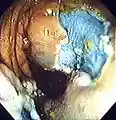

Colonoscopy being performed | |

Colonoscopy () or coloscopy ()[1] is the endoscopic examination of the large bowel and the distal part of the small bowel with a CCD camera or a fiber optic camera on a flexible tube passed through the anus. It can provide a visual diagnosis (e.g., ulceration, polyps) and grants the opportunity for biopsy or removal of suspected colorectal cancer lesions.